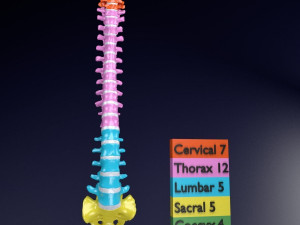

A blend model of brain along with its covering layers (meninges), skull bone and scalp labelled in detail and anatomically precise. The parts depicted are white, gray, pia, arachnoid, dura, bone, skin, fat, aponeurosis, periosteum, falx cerebri and more.